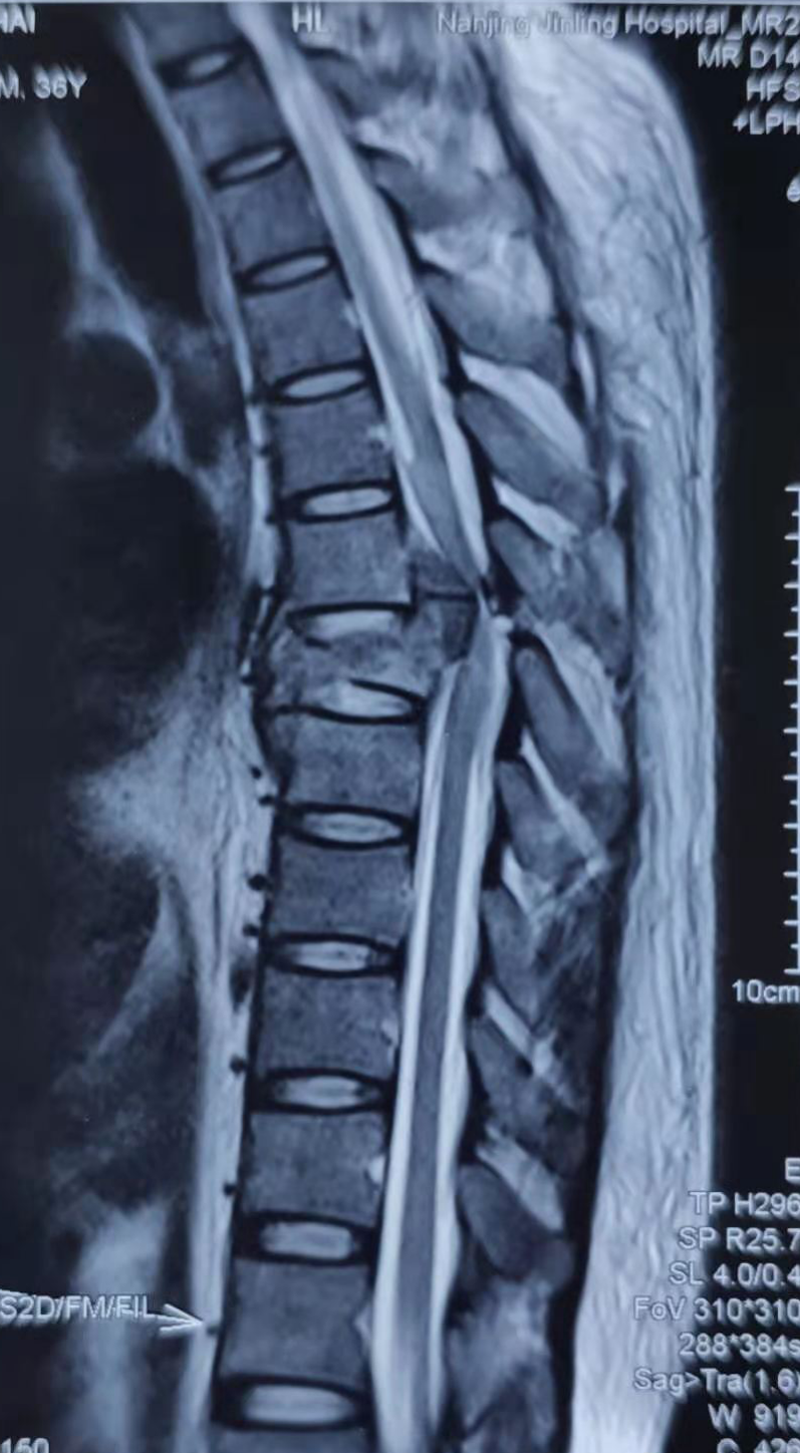

說起閆某的遭遇令人唏噓。他在礦井工作時,不幸被落下的碎石砸傷,導(dǎo)致胸椎、腰椎、肋骨、小腿多處骨折。由于病情危重從縣醫(yī)院轉(zhuǎn)往南京某醫(yī)院搶救,病情穩(wěn)定后經(jīng)歷了“后路胸椎骨折減壓復(fù)位植骨內(nèi)固定術(shù)”和“后路腰椎骨折切開減壓復(fù)位內(nèi)固定+左側(cè)腓骨骨折切開復(fù)位內(nèi)固定術(shù)”,身體里裝滿了螺釘鋼板。經(jīng)歷過生死考驗后,閆某第八胸椎以下感覺活動完全消失(雙下肢肌力0級,大小便失禁)。也就是醫(yī)學(xué)上說的“截癱”。閆某剛?cè)肟祻?fù)醫(yī)學(xué)科時,只能平躺,腰背部疼痛,雙下肢肌張力高,像“棍子”一樣僵直無法分開,輕輕觸碰就會抖動、痙攣。